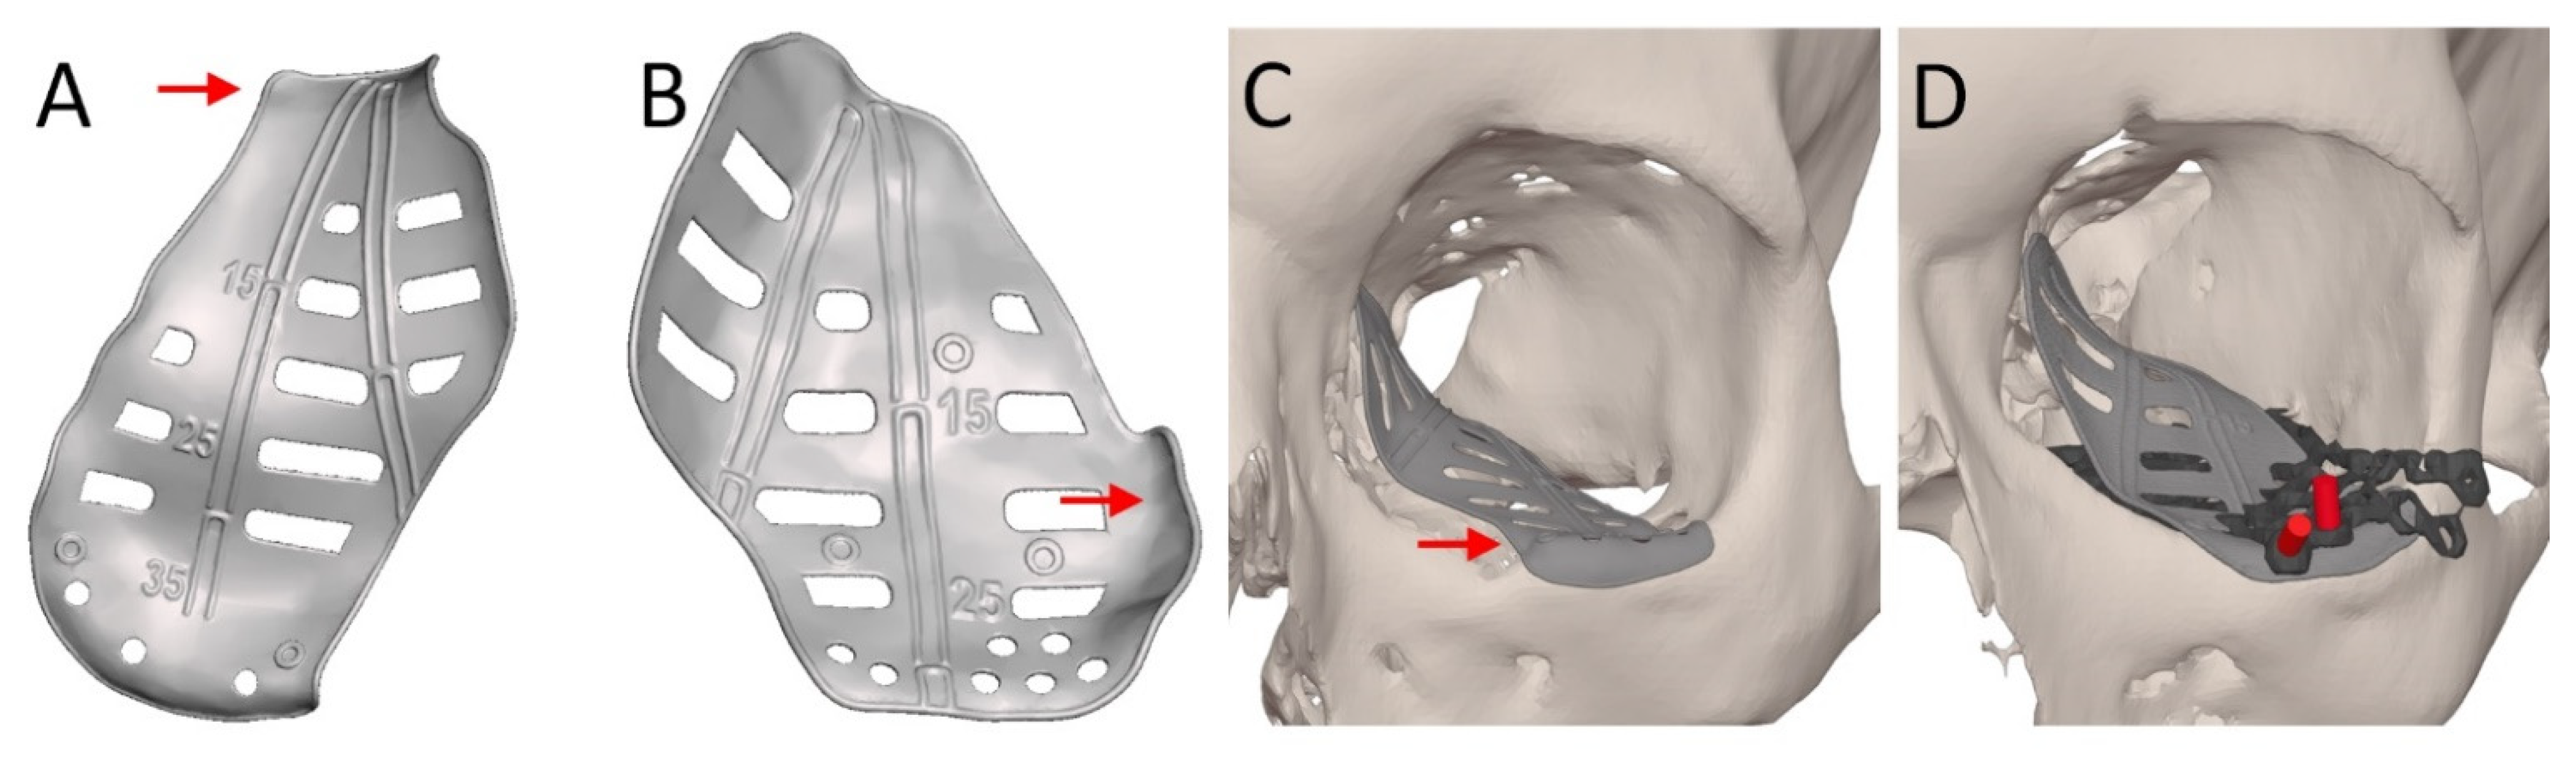

2.4. Patient-Specific Implant Design